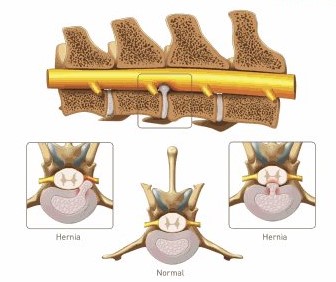

Les hernies discales sont très communes. Elles surviennent plus fréquemment chez des chiens de petite race d’âge moyen mais peuvent occasionnellement être vues chez des chiens de grande race et les chats. Il s’agit de la protrusion d’un disque intervertébral dans le canal vertébral comprimant ainsi la moelle épinière.